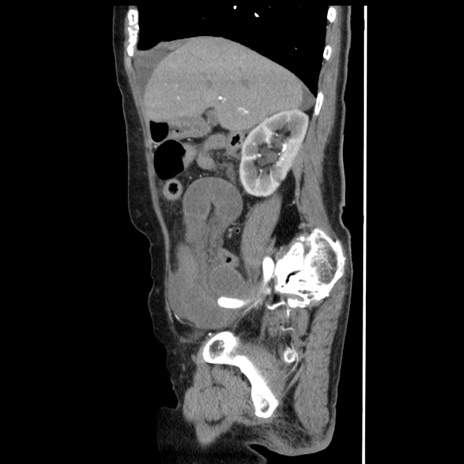

症例1(矢状断像)

【症例】80歳代女性

【主訴】腹痛

【現病歴】8時間前から腹痛あり来院。

【既往歴】糖尿病、脂質異常症、子宮体癌にて子宮全摘術

【身体所見】意識清明・会話良好だが腹痛で苦悶様、全腹部にわたって反跳痛と圧痛あり

【データ】WBC 13600、CRP 0.14、LDH 224、CK 90